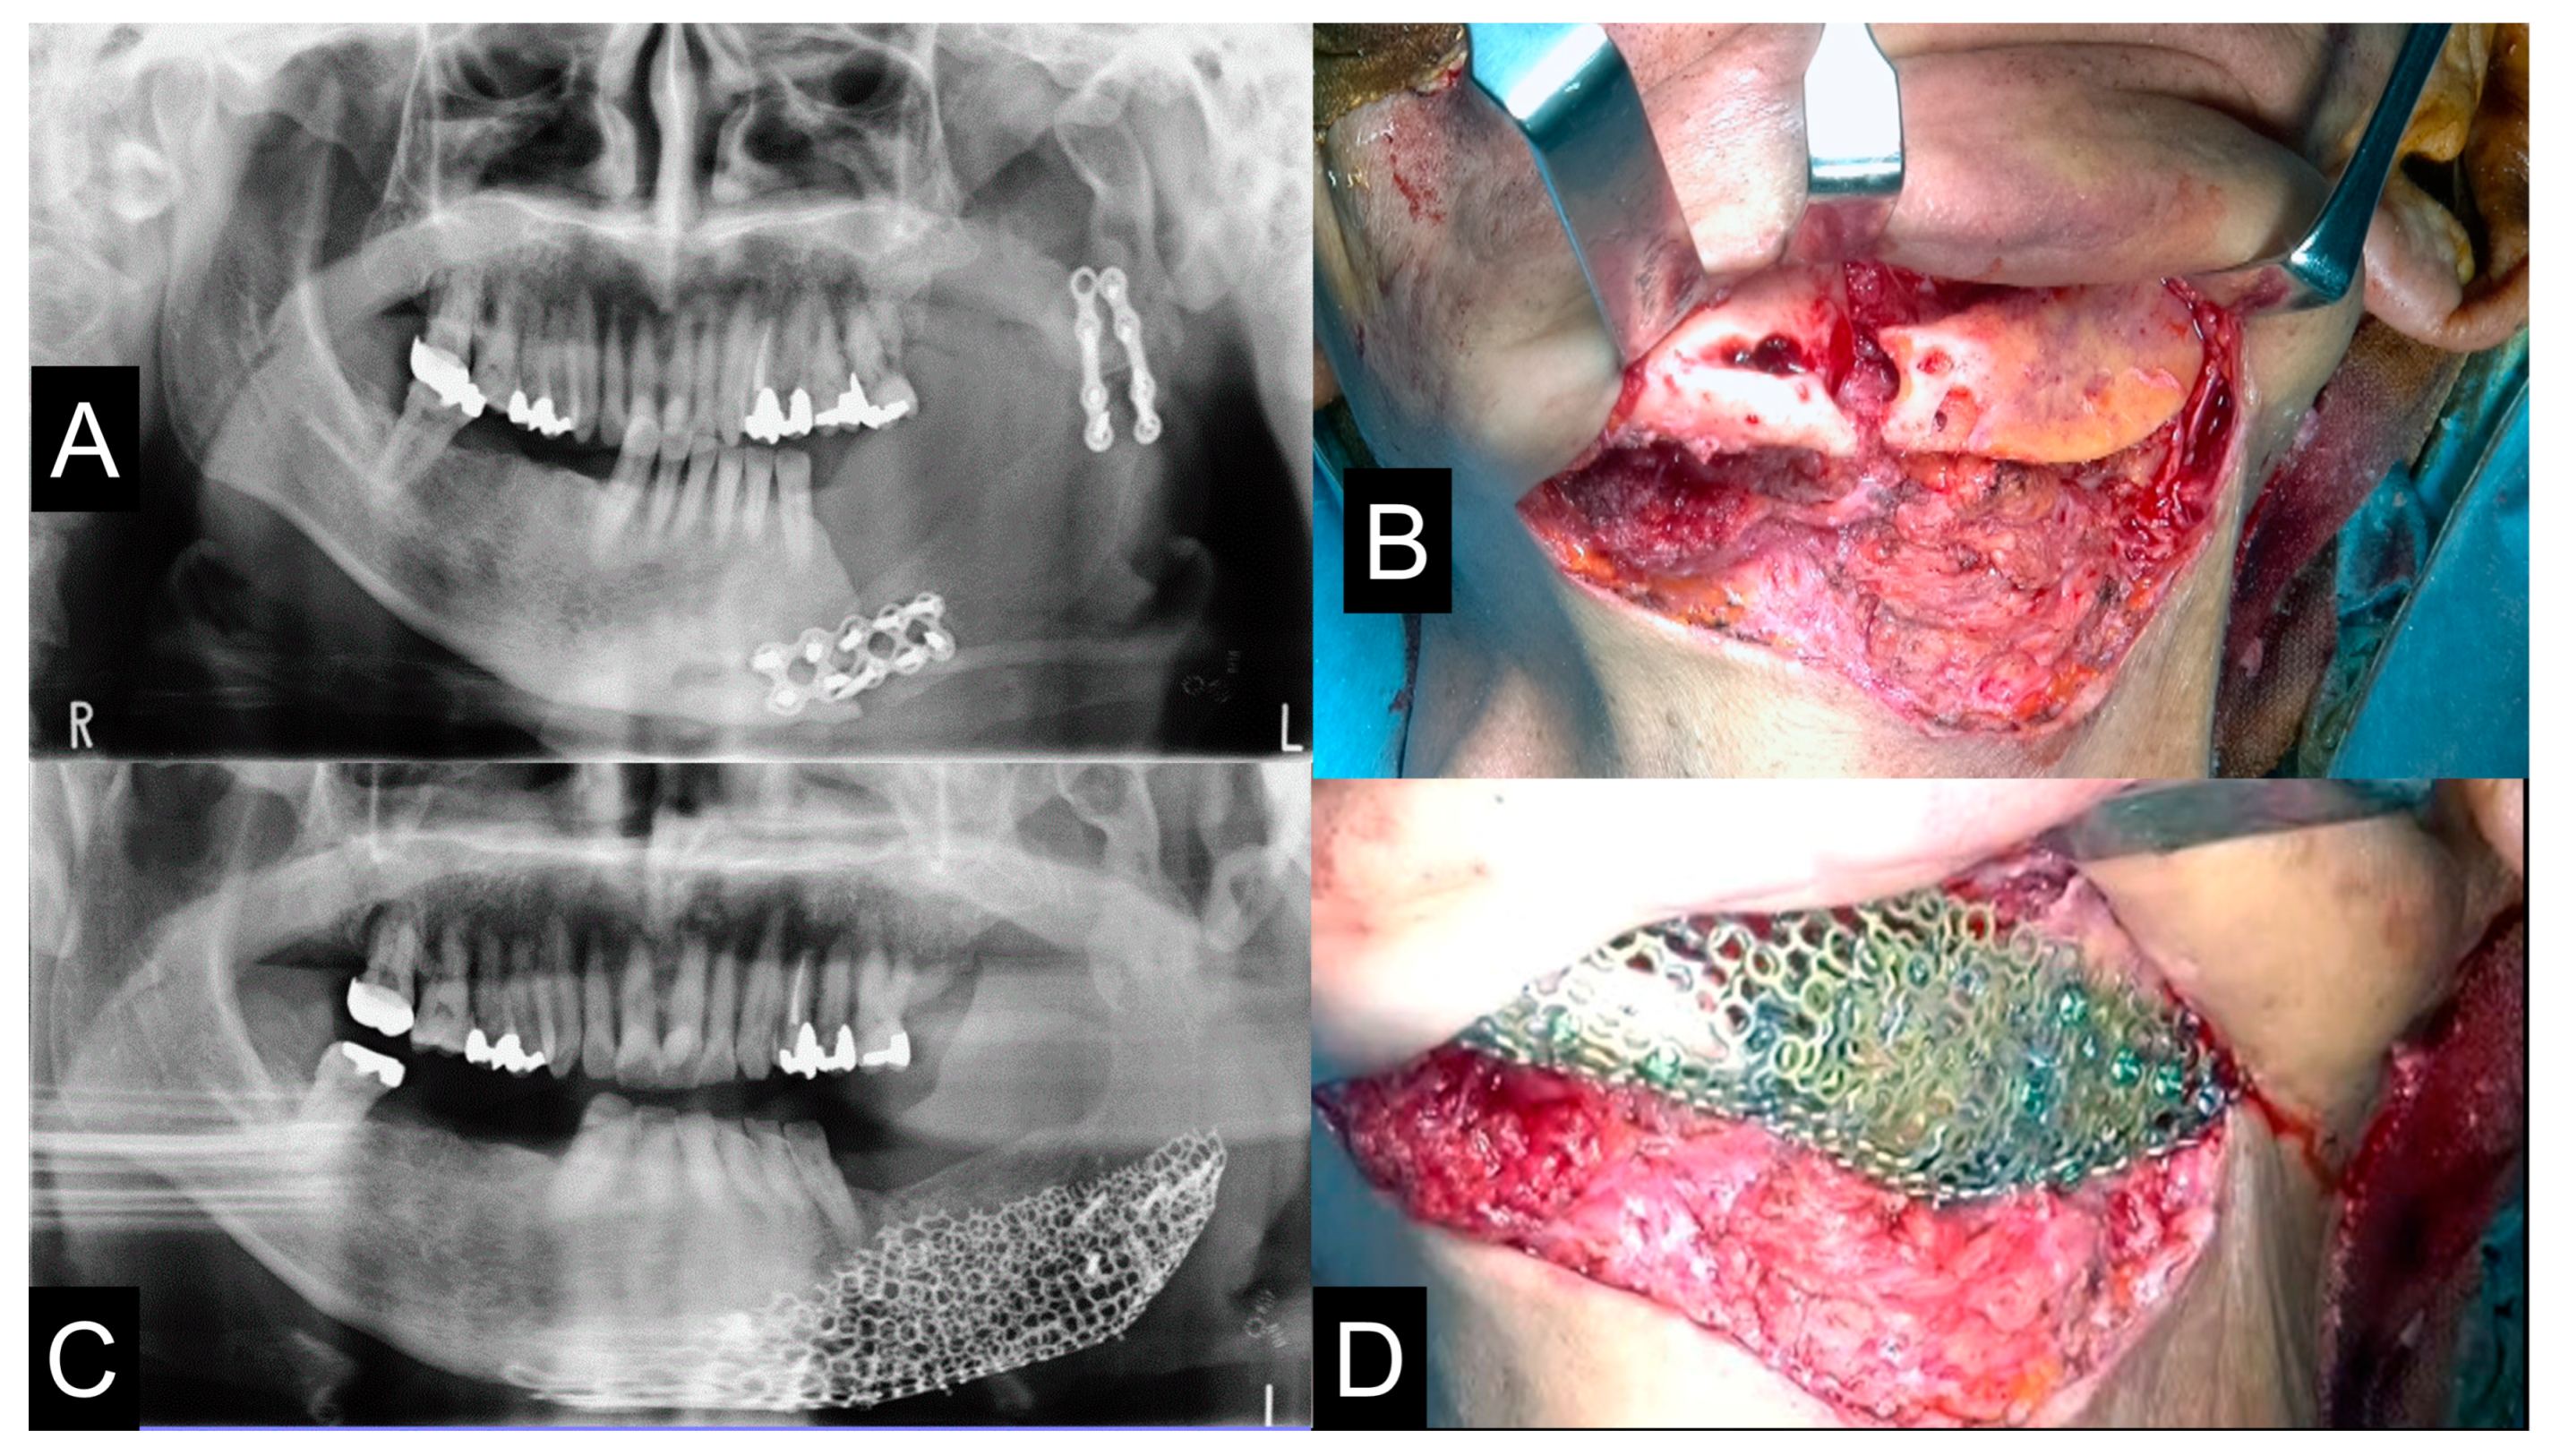

2.8. Clinical Procedures

2.5. 3D Printing Model Fabrication and Titanium Mesh Pre-Bending